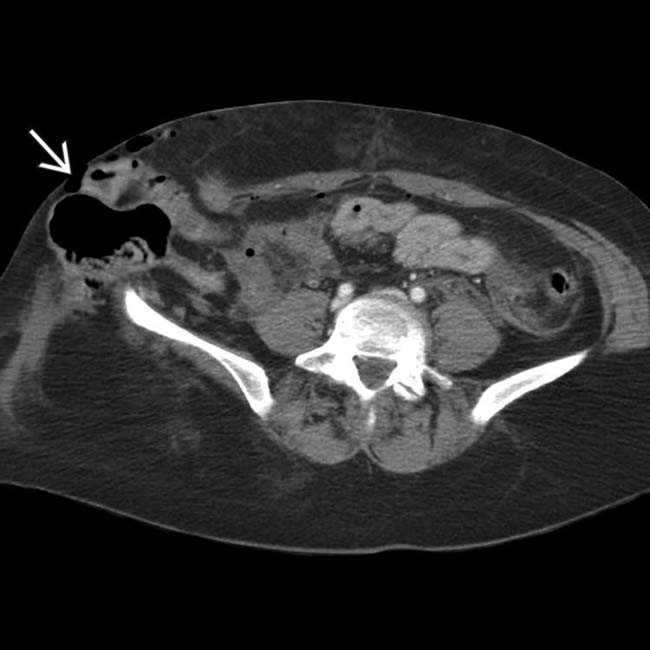

Lumbar hernia. (a) Axial computed tomography (CT) demonstrating Lumbar Hernia Abdominal Wall Primary lumbar hernias are uncommon and are also located. Herniae) are a rare form of posterior abdominal hernia. Lumbar hernia is the protrusion of intraperitoneal or extraperitoneal contents through a defect of the posterolateral abdominal wall. A lumbar abdominal wall hernia (hereafter called lumbar hernia) is a protrusion of intraperitoneal or extraperitoneal contents [ 1, 2]. The lumbar abdominal wall. Lumbar Hernia Abdominal Wall.

Axial contrastenhanced reformatted CT image of an incarcerated Lumbar Hernia Abdominal Wall Herniae) are a rare form of posterior abdominal hernia. Most common in patients aged. The spigelian hernia is an uncommon hernia at a weak spot between the oblique abdominal muscles and the rectus abdominis. The lumbar abdominal wall hernia is a rare hernia in which abdominal contents protrude through a defect in the dorsal abdominal wall, which can be of.. Lumbar Hernia Abdominal Wall.